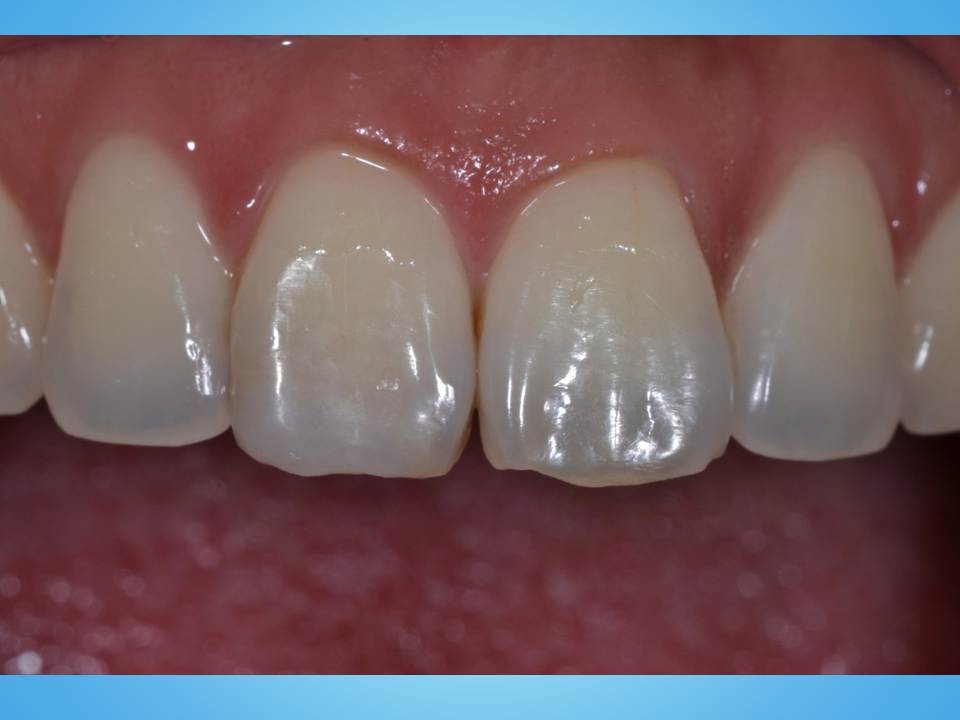

35歳女性。審美障害を主訴に来院しました。

↑初診時の写真です。

左側の歯の先端に人工の詰め物が認められ、変色と形態不良が著しい状態でとても気にされていました。

審美修復する方法が何種類かありますが、今回は部分的な詰め物で治療することとしました。